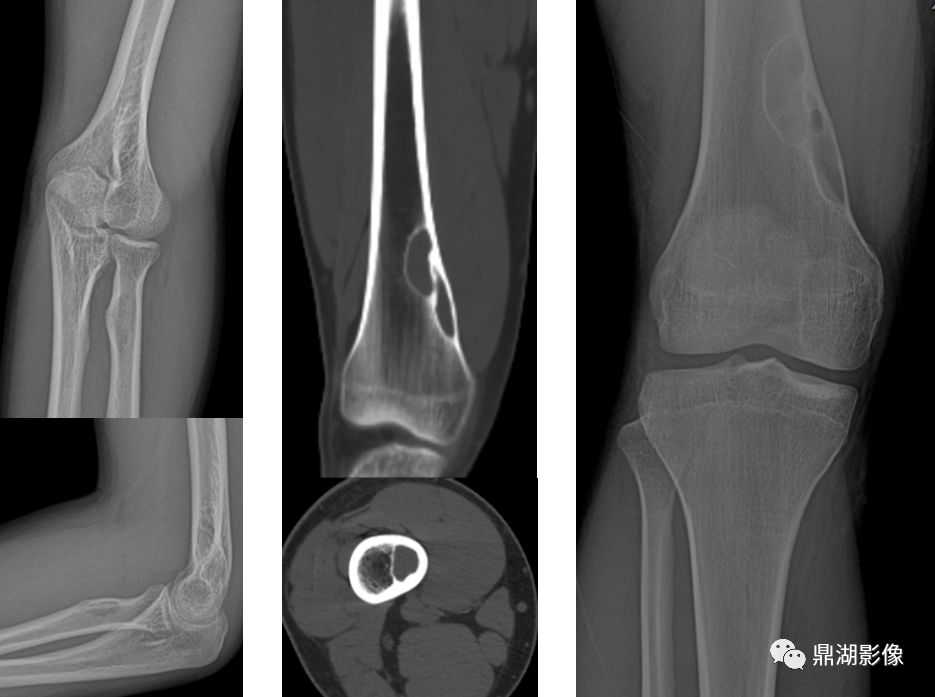

骨样骨瘤

由于成骨细胞及其它骨样组织畸形生长所导致的成骨性肿瘤

常见于30岁以下的青少年

好发于股骨小粗隆、肱骨近端内侧皮质、胫骨远端1/3

多位于骨皮质,骨样组织构成的“瘤巢”(骨质破坏环)及周围的反应硬化

疼痛以夜间明显,口服水杨酸制剂有效

骨软骨瘤

最常见的良性骨肿瘤,又称外生性骨疣。发生于软骨内化骨的骨骼

以四肢长骨干骺端多见,可分为单发和多发两种,单发者多见

肿瘤由骨性基底和软骨帽构成,多背向关节生长,骨皮质和骨小梁与骨干相延续

骨巨细胞瘤

是一种局部侵袭性肿瘤,大部分为良性,部分生长活跃,也有少数一开始就是恶性

男女发病率相近,好发年龄是20-40岁

好发于骨骺板已闭合的四肢长骨骨端,尤其是股骨远端、胫骨近端和桡骨远端

膨胀性多房性偏心性骨破坏,横向生长

分房状或皂泡状,骨破坏区无钙化和骨化影